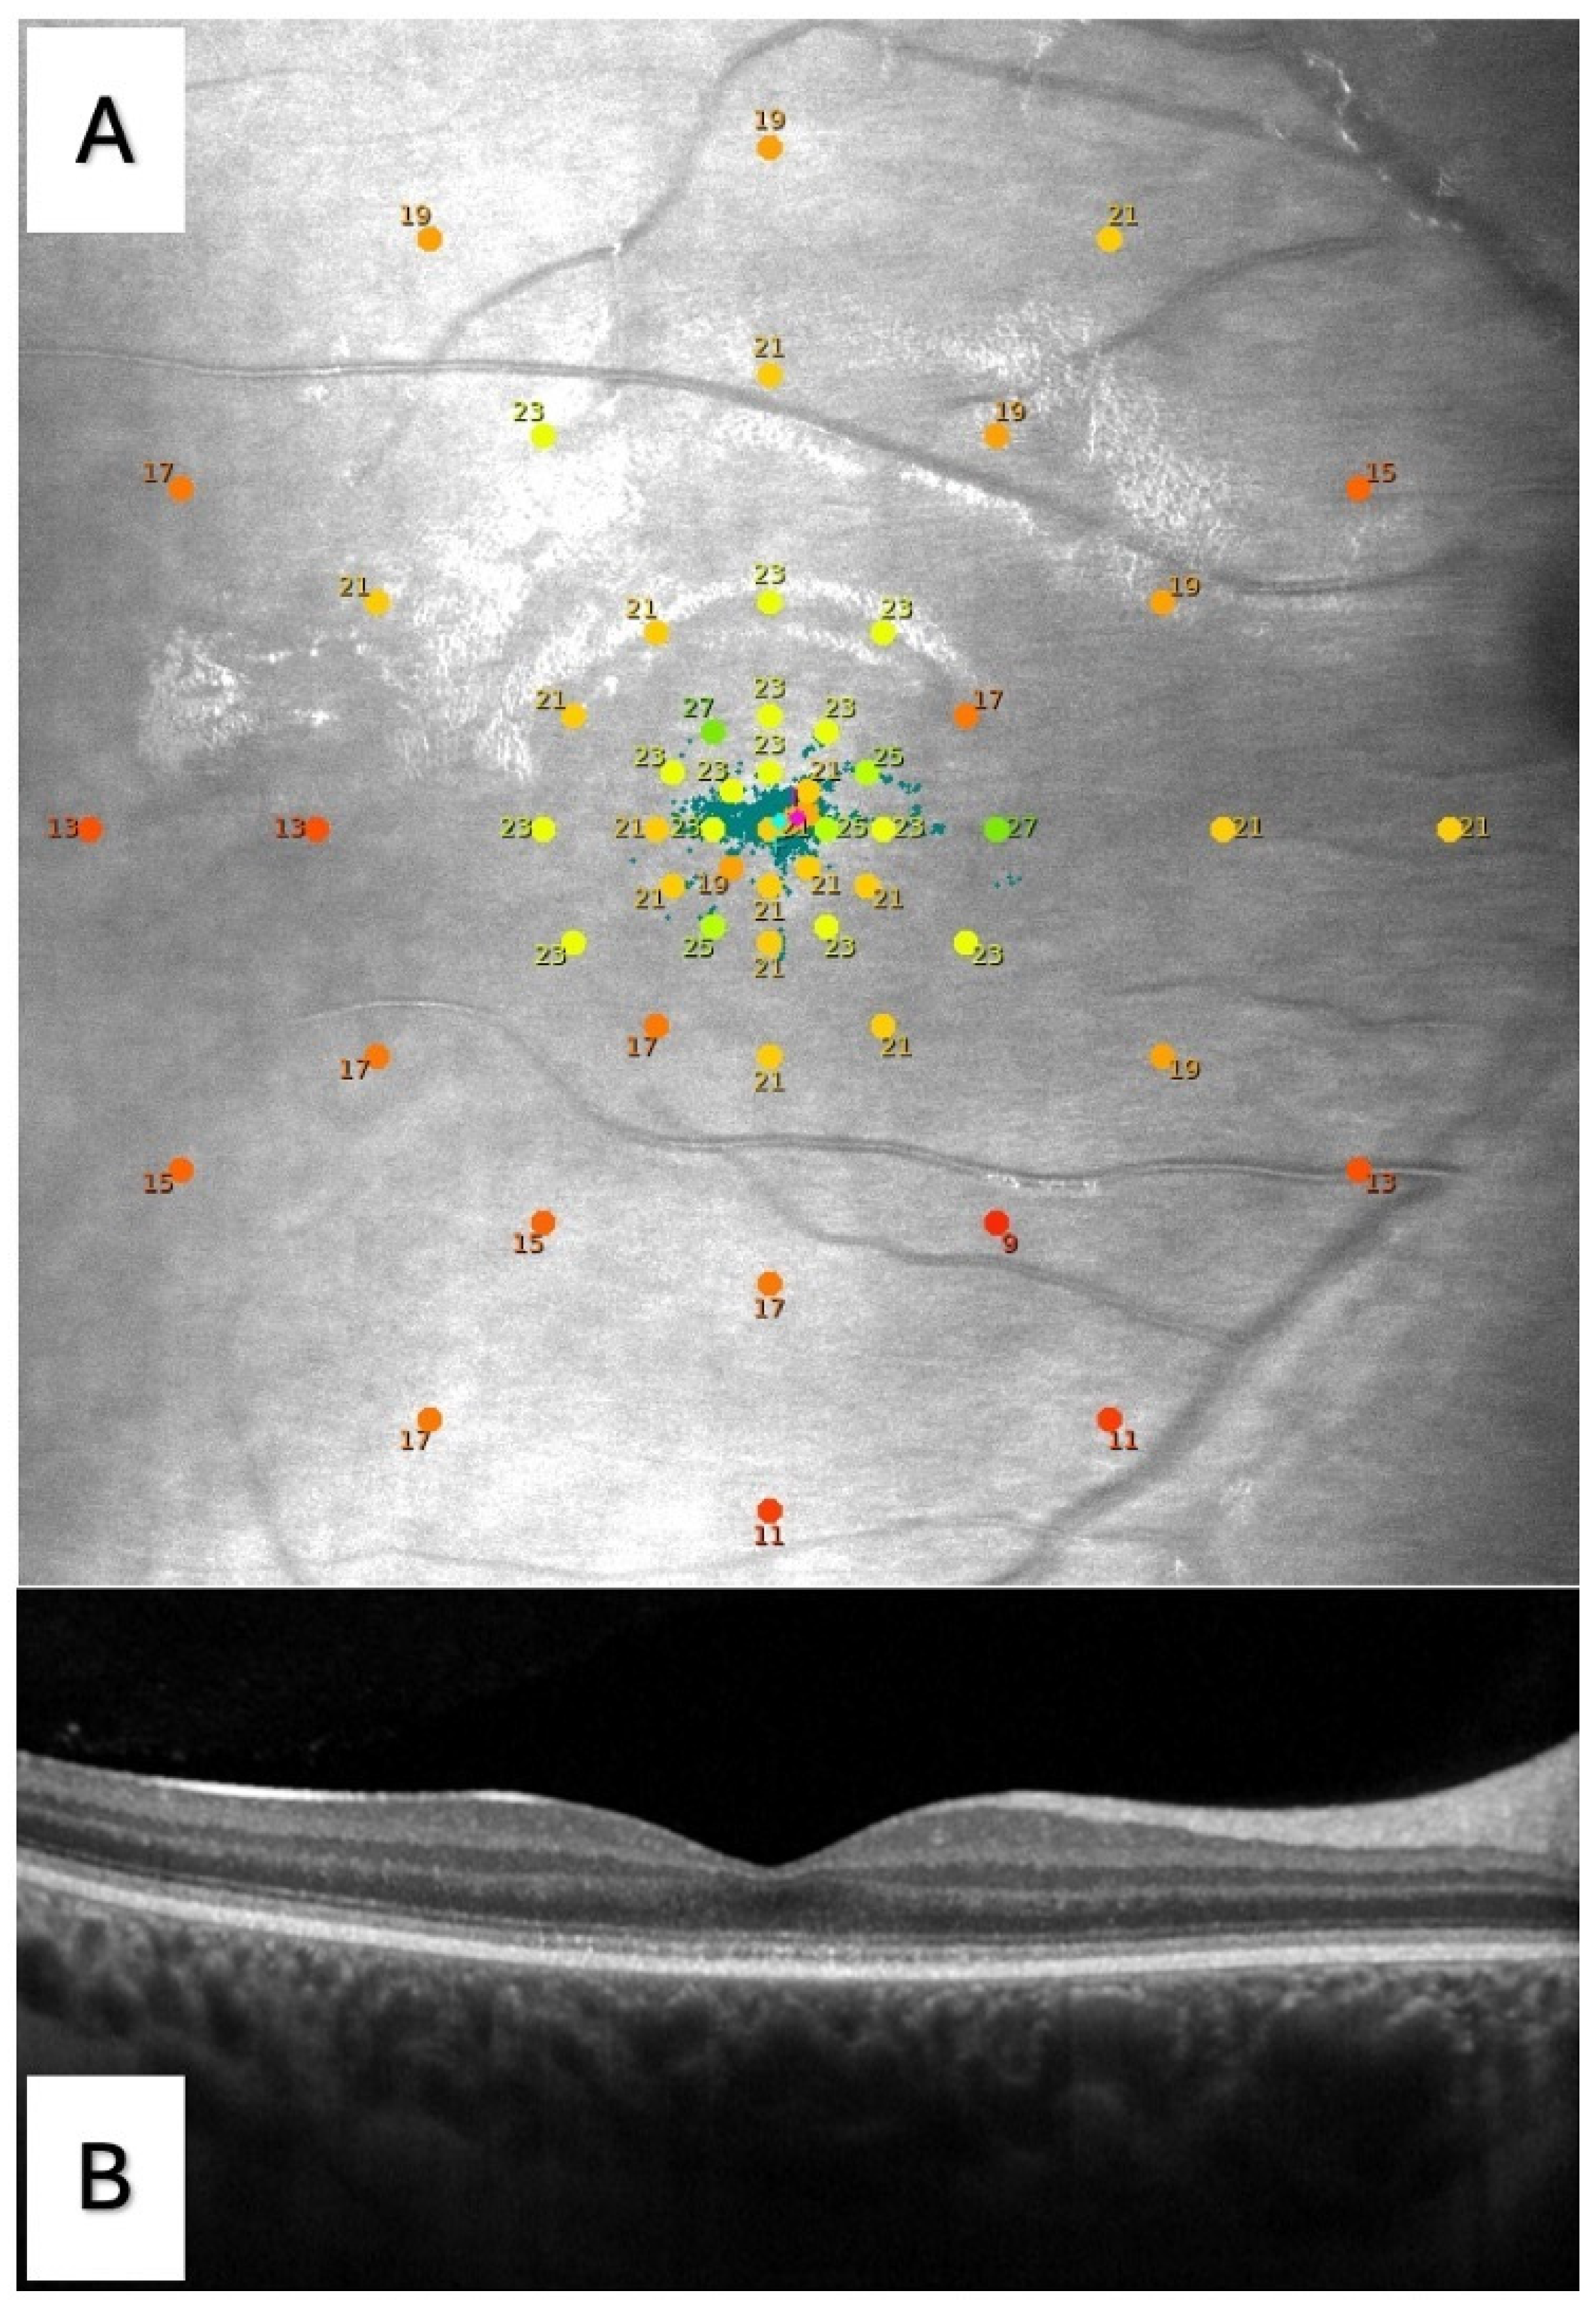

| Microperimetry | |

| BCEA63, degree2 | 13.0 ± 16.0 |

| BCEA95, degree2 | 39.0 ± 47.9 |

| AS, dB | 21.2 ± 2.7 |

| C, dB | 20.4 ± 6.6 |

| R1, dB | 20.8 ± 5.9 |

| R2, dB | 21.1 ± 4.7 |

| R3, dB | 23.1 ± 2.0 |

| R4, dB | 21.5 ± 2.9 |

| R5, dB | 20.2 ± 2.7 |